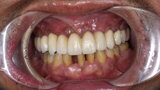

Compromised maxillary dentition treated with Straumann Pro Arch and a digital workflow